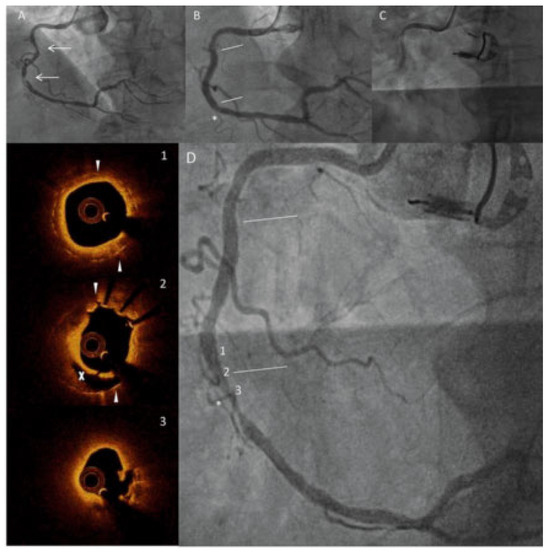

Geographic miss leading to neoatherosclerosis and very late stent thrombosis

by Mehdi Madanchi, Giacomo Maria Cioffi, Adrian Attinger-Toller, Richard Kobza, Matthias Bossard and Florim Cuculi

Cardiovasc. Med. 2022, 25(2), 62; https://doi.org/10.4414/cvm.2022.02195 (registering DOI) - 1 Mar 2022

Viewed by 62 Show Figures

Figure 1